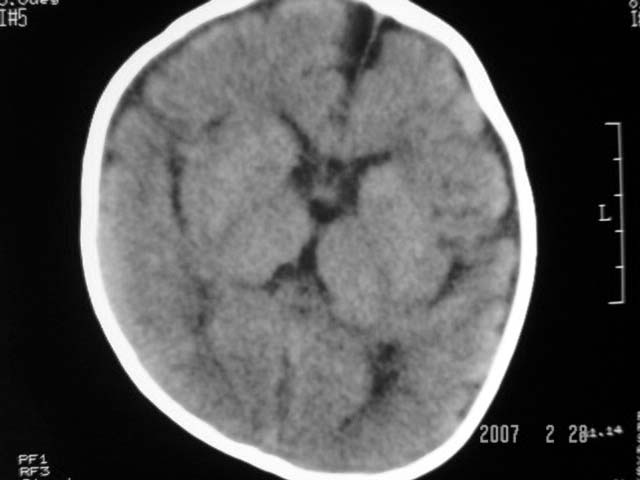

标题: PED0015:男,8M,发现不会坐立及神情异常,前囟已闭,双眼斜视,

脑回较深,白质范围小,灰白质比例失调。余未见明显异常。

考虑:脑白质发育不良,必要时请做mri进一步检查。